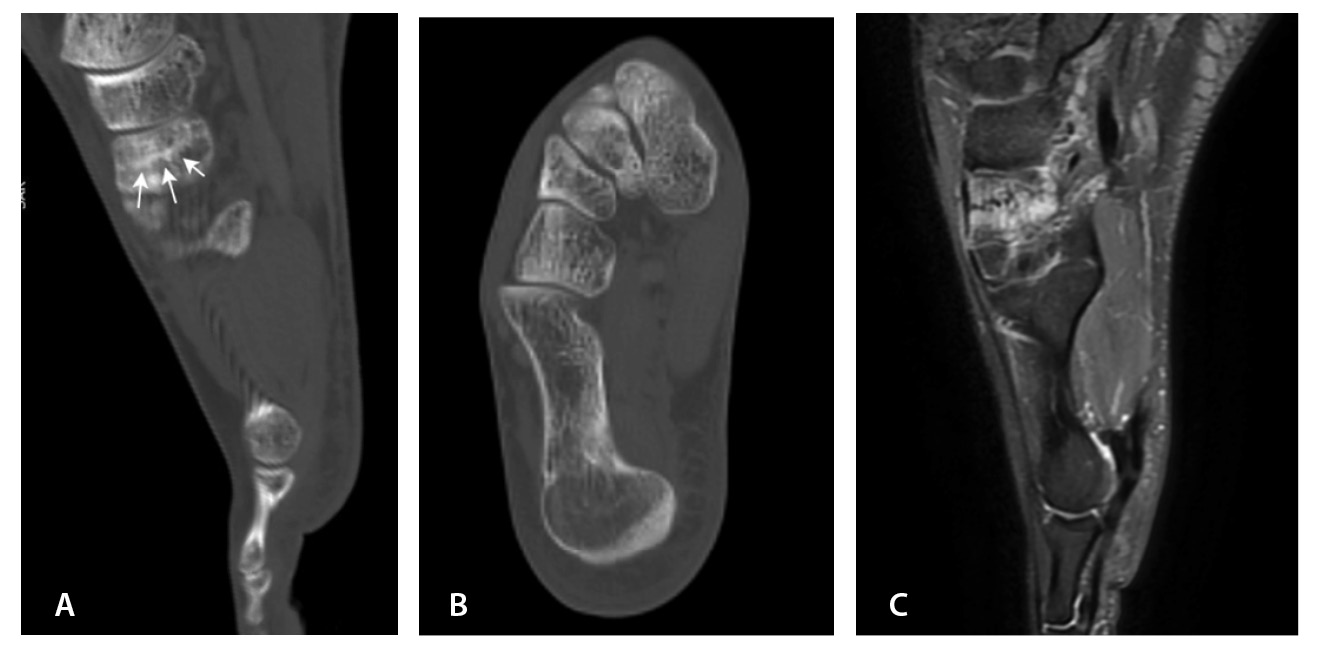

МРТ – наиболее подходящий метод визуализации остеохондрального повреждения купола таранной кости с чувствительностью и специфичностью 96% [52]. В исследованиях M. Haubro и соавт. [53], M. P. Wilson и соавт. [28] МРТ квалифицирована как золотой стандарт диагностики скрытых переломов по сравнению с КТ и рентгенографией. Протокол, состоящий из корональных T1-взвешенных изображений и STIR, обладает 100% чувствительностью в выявлении рентгеннегативных переломов (рис. 3) [28].

МРТ – первоначальный метод диагностики при подозрении на стрессовые переломы, так как ранним признаком таких переломов служит отек костного мозга пораженной кости, ярко выделяющийся среди остальных неизмененных костей. Отсутствие визуализации костного мозга затрудняет диагностику такого рода повреждений при рентгенографии и КТ (рис. 4). Чувствительность МРТ в выявлении стресс-переломов достигает 99% (95–100%), а специфичность – 97% (88–100%). Несмотря на то что исторически сцинтиграфия была основным методом обнаружения стресс-переломов с почти 100% чувствительностью, в настоящее время выполнение радионуклидного метода не рекомендуется из-за его низкой специфичности и высокой дозы ионизирующего излучения [54].